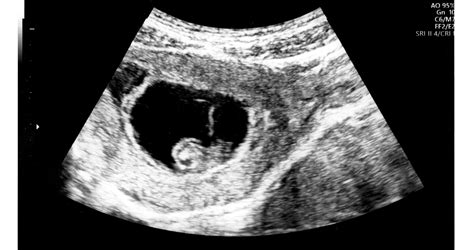

A magzatvíz a terhesség 9 hónapja alatt veszi körül a babát a méhen belül. Védi őt a külső hatásoktól, és fontos szerepe van a magzat fejlődésében is. Éppen ezért nagyon ijesztő lehet, ha a vizsgálaton kiderül, hogy túl sok vagy éppen túl kevés a magzatvíz.

A magzatvizet a magzatburok, a baba veséje és az anya vérplazmája termeli. Mennyisége a terhesség folyamán állandóan növekszik, a szülés előtti hetekben már 1-1,3 liter víz veszi körül a babát. A teljes vízmennyiség 3-4 óránként lecserélődik.

A magzatvíz nagyon sok funkciót tölt be a gyermek életében a terhesség ideje alatt. Oltalmat, védelmet és a fejlődéshez elengedhetetlen világot biztosít. Azonban ha a magzatvíz mennyisége nem megfelelő - túl sok vagy éppen túl kevés -, az számos probléma forrása lehet.

A terhesség során a magzat magzatvízzel körülvéve helyezkedik el az anyaméhben. Ez védi a fejlődő kis szervezetet a külső káros hatásoktól, biztosítja az állandó hőmérsékletet, és fontos szerepe van a tüdő fejlődésében is.

A magzatvizet a magzatburok (az amnion és a chorion), a magzat kültakarója, később veséje is termeli, valamint az anya vérplazmája is részt vesz a létrejöttében. A magzatvíz mennyisége a terhesség során fokozatosan növekszik, szülés előtt eléri az 1-1,3 litert! Mivel a magzatvíz rendszeresen - 3-4 óránként - kicserélődik, így könnyen érthető, hogy a magzatvízforgalomban bekövetkező bármely zavar a mennyiség gyors növekedését vagy csökkenését okozhatja.